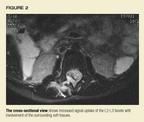

The MRI provides the long-awaited key to the diagnosis. An abnormal increasedsignal is found in the thecal space in the lumbar spine, suggesting a spinalepidural abscess or an infected hematoma (Figure 1). Hyperdense signalsare found at the level of the L2-L3 facets on the right and the surroundingsoft tissues (Figure 2).

MRI is the preferred imaging technique to uncover the possibility ofa spinal epidural abscess. CT scans with contrast may be helpful, but bonescans and plain radiographs are usually negative unless there is an associatedosteomyelitis.2 The management of this abscess in children isimmediate surgical drainage with laminectomy, and parenteral antibiotics.